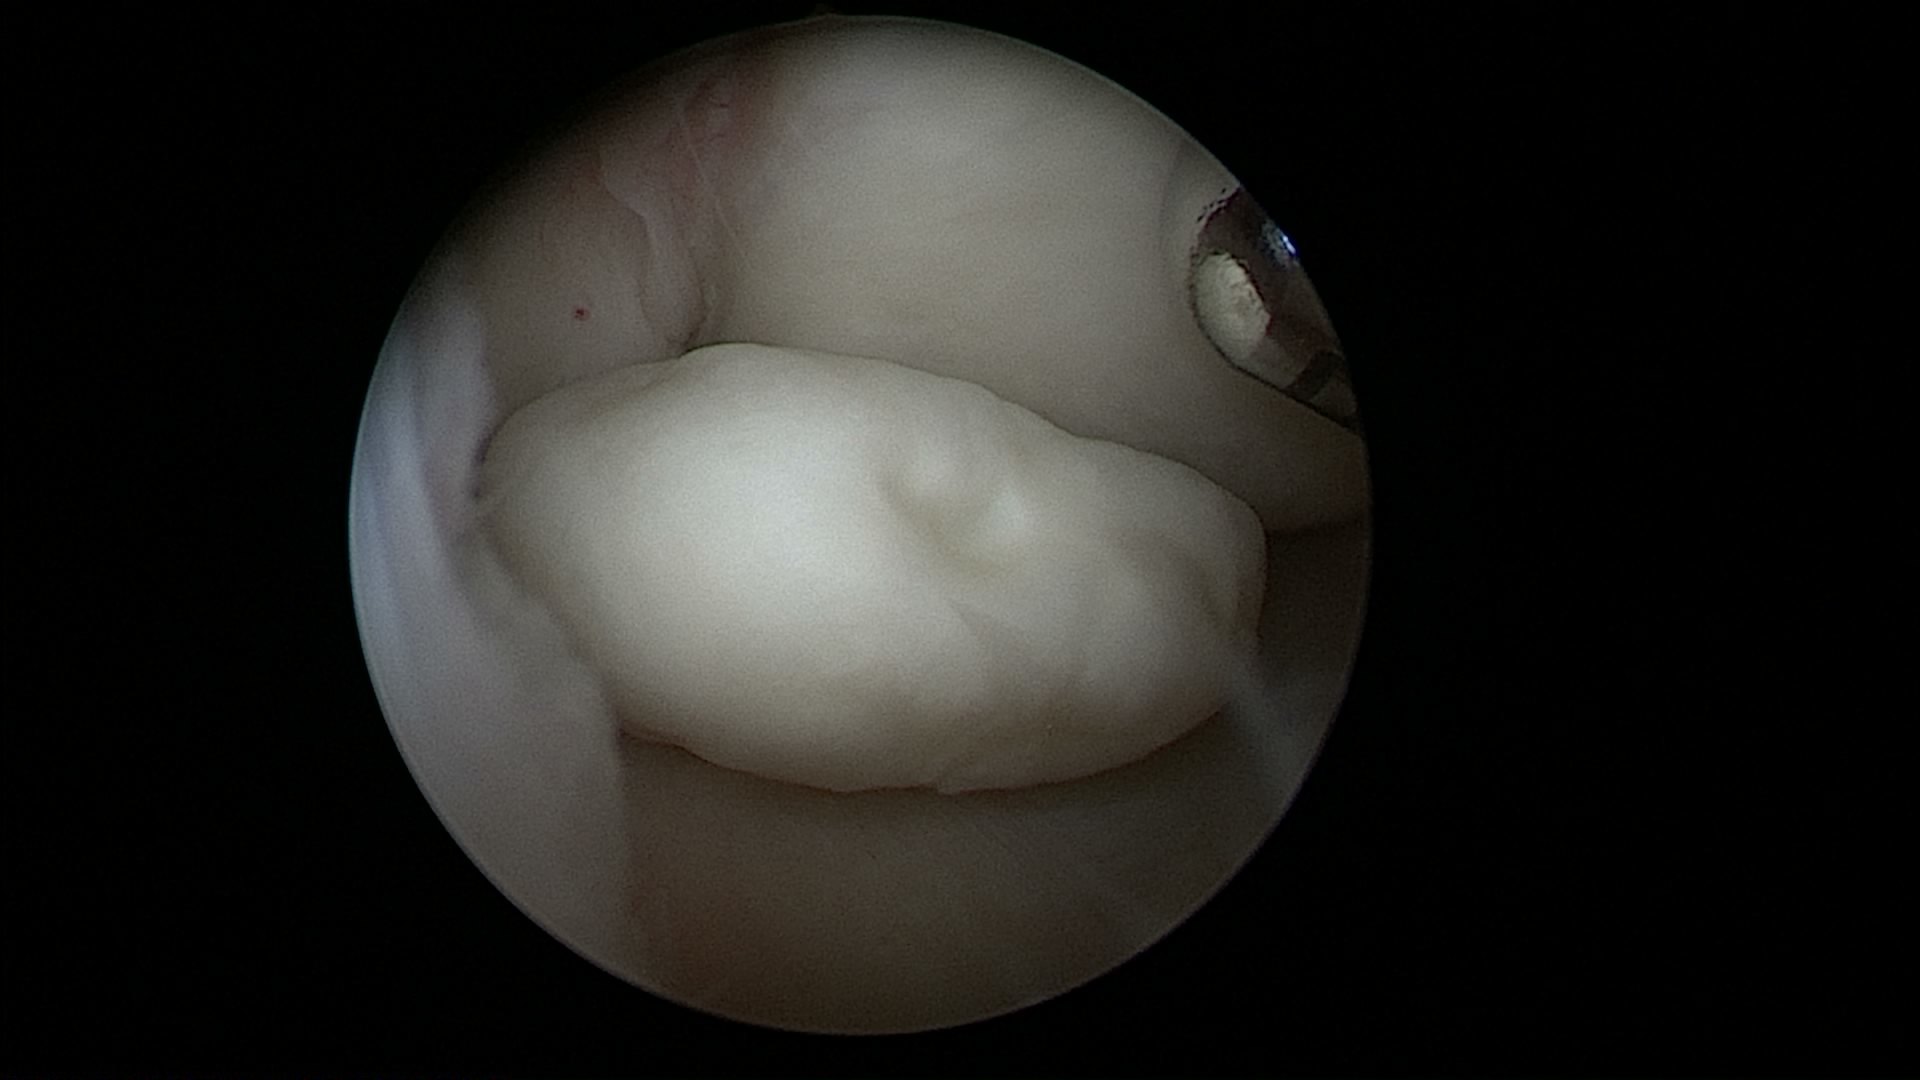

挖掘膝关节后室的"游离体" - 好大夫在线

微创治疗膝关节游离体取出术

图为患者镜下取出的游离体